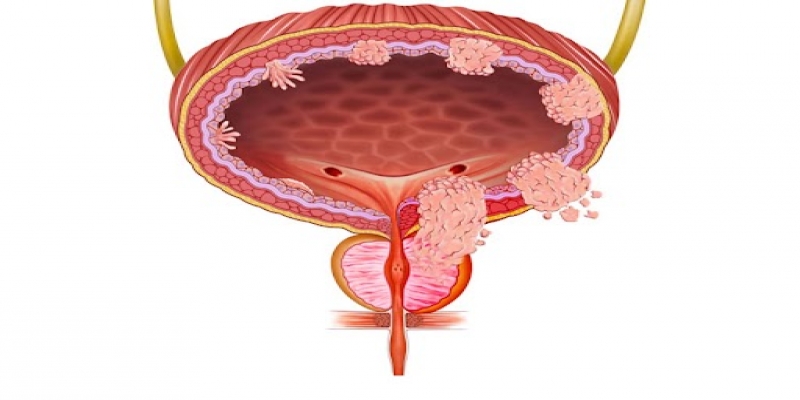

Specialized Surgeries by Dr. Harshit Srivastava

Dr. Harshit follows strict evidence-based protocols backed by the latest global guidelines. Every treatment plan is crafted using scientifically proven strategies to ensure the best possible outcomes for the patients.